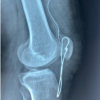

Case Report: The patient had a left total knee replacement one year previously and came in for her one-year follow-up. She presented 3 weeks after her injury with a high-riding patella and a small tibial tubercle avulsion fracture on X-ray, yet she did not experience much pain nor any loss of active extension of her left knee. Despite the severity and subacute presentation of the patient’s patellar tendon injury, conservative measures that included physical and occupational therapy was recommended instead of surgery due to her paradoxical retention in gross function of her left knee.

The patient is a 75-year-old female with a past medical history of hypertension, chronic obstructive lung disease, and emphysema. She has a past surgical history of bilateral total knee replacements: the right knee was replaced two years ago, and the left knee was replaced one year ago. There were no complications with either procedure. She presented for her yearly follow-up complaining of new onset of 1 out of 10 left knee pain with mild weakness and difficulty climbing stairs. The patient stated that she fell 3 weeks prior to her visit, complaining of moderate pain and swelling for 1-2 weeks that subsided substantially. She did not seek immediate medical attention. Before her fall, she was functioning normally with no pain. On exam, she had a slightly antalgic gait, ambulating without any assistive devices. She had full range of motion and strength of both hips, knees, and ankles with mild swelling and ecchymosis over the left tibial tubercle and minimal tenderness (as seen in Fig. 1-2).